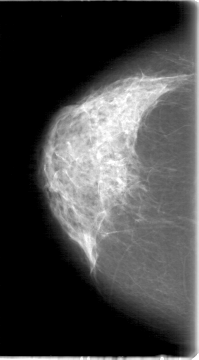

D_4088_1.LEFT_CC

LEFT_CC LINES 5386 PIXELS_PER_LINE 3226 BITS_PER_PIXEL 12 RESOLUTION 43.5 NON_OVERLAY